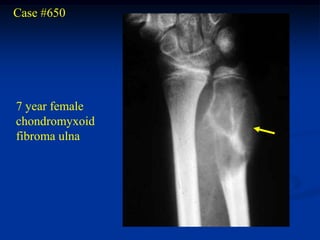

Case #650

7 year female

chondromyxoid

fibroma ulna

Photomic